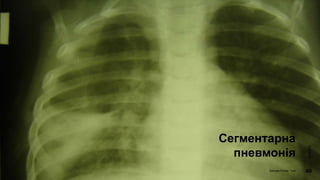

Клініка

Сегментарна

пневмонія

Рентгенографія легень

• рентгенологічна картина залежить від фази розвитку

запального процесу. В період вираженої клінічної

картини виявляють вогнищеві тіні різних розмірів ,

частіше розміщених локалізовано.

• При сегментарних пневмоніях – гомогенна тінь з чіткими

контурами в межах сегменту